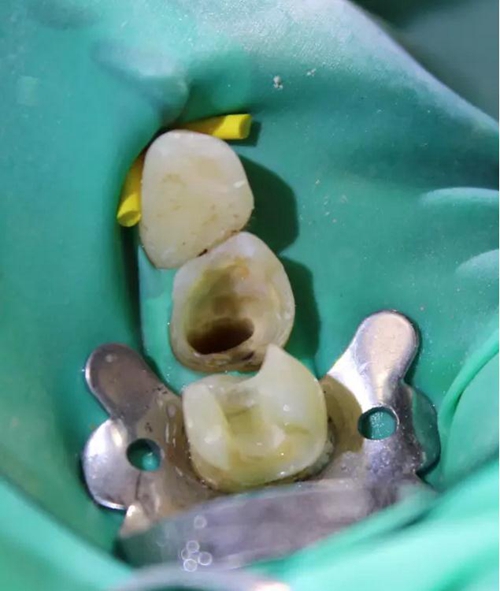

圖3 核修復(fù)完畢(橡皮障未去除)。這種2層堆疊技術(shù)非常快速,且調(diào)(牙合)更少。